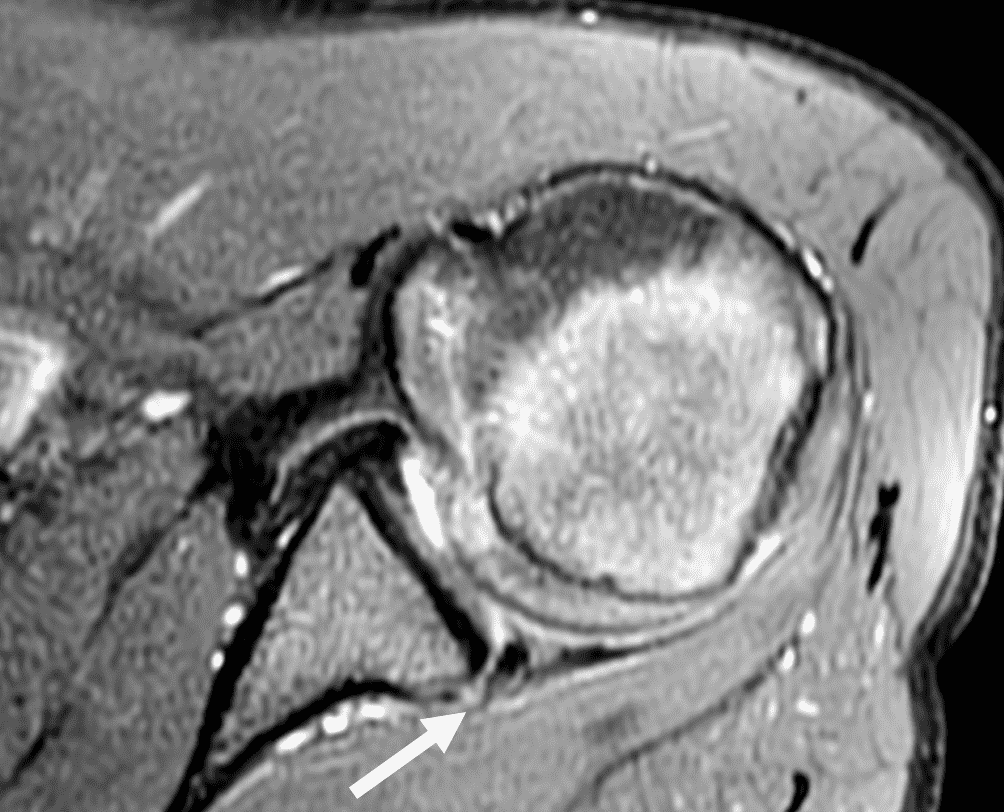

20 year old right-handed hitting college baseball player with left shoulder injury. Fat-suppressed proton-density-weighted axial images at the mid (1A) and inferior (1B) left glenohumeral joint are provided. What are the findings? What is your diagnosis?

Figure 2: The axial images (2A and 2B) demonstrate findings of a posterior glenohumeral instability injury including posterior to posteroinferior capsulolabral tearing and pericapsular edema (solid arrows) and an anteromedial humeral head impaction injury (dashed arrows).